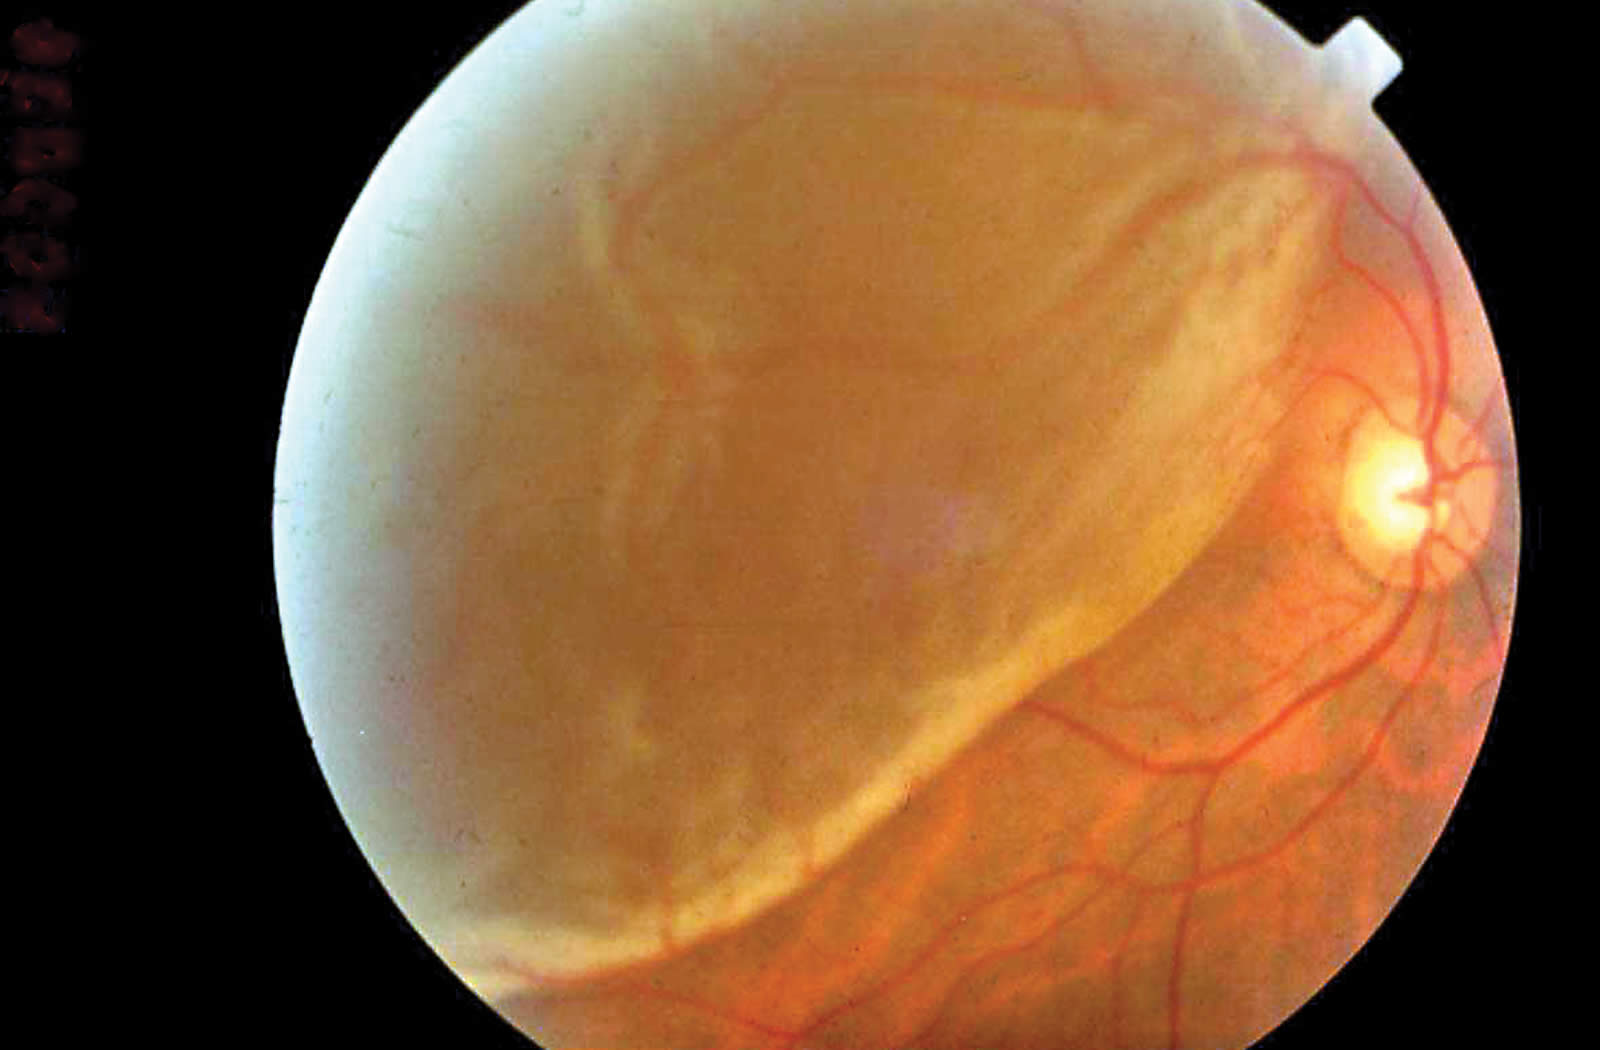

Fig 1. Recent subtotal rhegmatogenous retinal detachment. © Subhadra Jalali

1. Rhegmatogenous retinal detachment (RRD) where the RD develops due to a retinal break (‘rhegma’, meaning a rent or a fissure) (Figure 1). Fluid, from the vitreous cavity, passes through the retinal break into the potential space under the retina, leading to separation of the retina from the underlying choroid. This requires surgical treatment.

The best method of diagnosing RD is by binocular indirect ophthalmoscopy with scleral indentation. An obvious RD is recognised by loss of the red fundus reflex and marked elevation of the retina (Figure 1). The retina appears grey, and shows folds and undulations. Shallow detachments are difficult to diagnose but can be seen with stereoscopic visualisation of the retinal vessels that cast a shadow on the underlying retinal pigment epithelium (Figure 2).